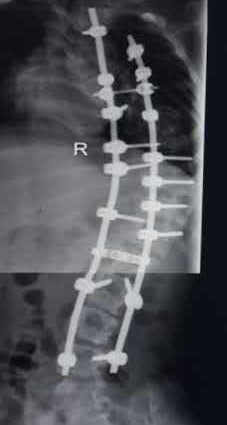

手术由贺西京、李浩鹏教授亲自主刀,并邀请有丰富麻醉经验的李有才教授负责麻醉,在严密的诱发电位全程监护下施行全脊柱截骨矫形术。即将脊椎一节节打断、截骨,再重新排列、固定。因脊柱畸形严重,常规固定方式无法完成,只能凭经验探索进行,并多次进行术中透视,确保矫正角度。如此大范围脊柱矫形,风险极大,术中稍有不慎,无论是术中操作,还是骨片,都有可能损伤血管造成大出血,危及生命。因手术创伤大,时间长,出血多,术中患儿多次出现心率加快、烦燥等症状,通过及时的输血、补充血容量后好转。在完成椎体截骨时,脊髓也要完成近120度的变位,此时极易损伤神经,风险极大。神经损伤会造成患儿终身瘫痪,双下肢丧失运动、感觉功能,并出现大小便失禁等,因此要求术者一定要心细,操作要轻、准。并通过诱发电位,及时反复监测神经传导速度,判定神经功能。在手术、麻醉及护理人员的紧密配合下,经过近10小时紧张、细致的手术,手术取得成功,矫形由患儿颈后部到腰下段的脊柱全段,缝合30余针,术中输血1800毫升,术中矫正脊柱畸形角度约120度。术后患儿即可平卧,背部的罗锅畸形显著改善,双下肢感觉、运动良好,自解小便,身高由术前的130cm增加到142cm。患儿及家属对手术效果非常满意。